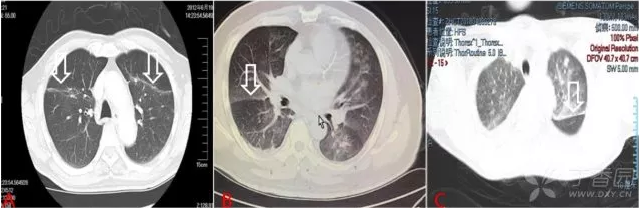

圖 2  心源性肺水腫典型表現(xiàn):袖套征

圖 2A1 為正常肺組織 CT 成像,圖 2A2 所示為同一患者發(fā)生心力衰竭后復(fù)查,同一部位支氣管血管束明顯增粗(白細(xì)箭),同側(cè)可見少量胸腔積液(黑曲箭)

圖 2B、C 可見更加明顯的支氣管壁增粗,形成明顯的袖套樣改變(圖 2B 白細(xì)箭,圖 2C 黑粗箭),圖 2C 中可見明顯的小葉間隔增寬。